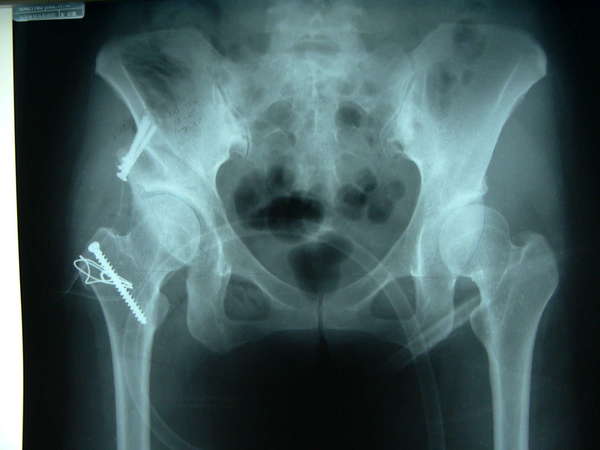

经过手术后髋臼对股骨头的包容与覆盖矫正